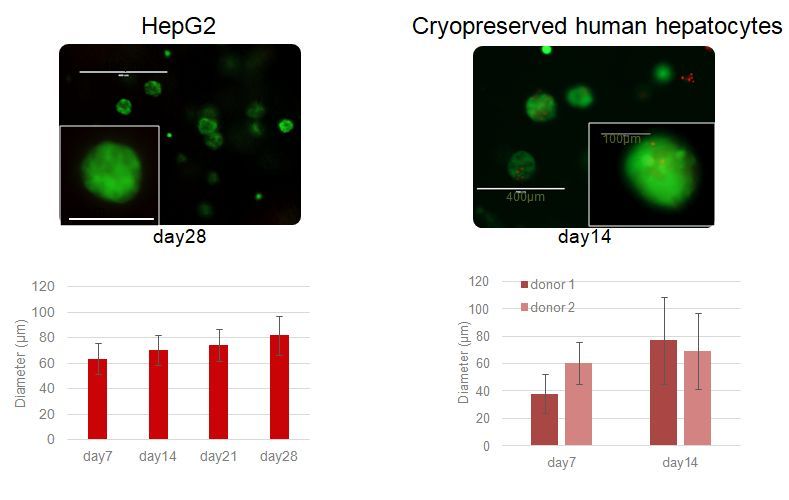

Spheroid: Viability&Growth: Increase Culture Time

Primary human hepatocytes and hepatocarcinoma cell line, as HepG2, remain viable for longer time in culture compared to 2D. Furthermore, primary human hepatocytes keep their metabolic activity for longer time in culture compared to 2D, even in sandwich culture.